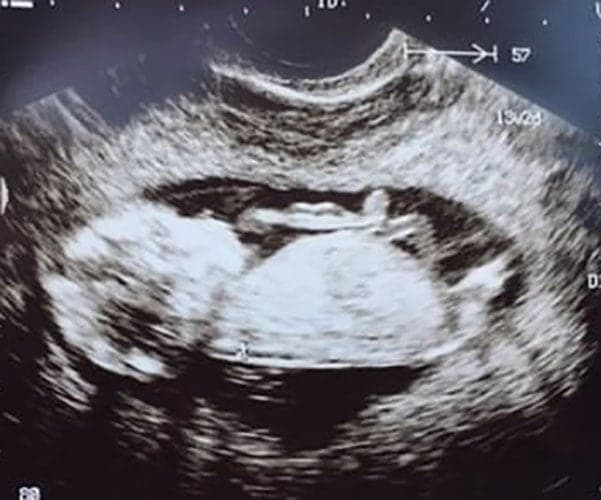

Ultraschallbilder aus dem 2. Trimester (13. bis 28. SSW)

Im 2. Trimester bekommt man oft die schönsten "Ganz-Körper" Ultraschallbilder. Das Baby ist nun so groß, dass man alles gut erkennen kann und noch nicht zu groß, so dass es noch ganz auf das Bild passt. In dieser Zeit lässt sich meist das Geschlecht bestimmen, wobei manche Babys es einfach nicht preis geben wollen und sich immer so drehen, dass man nichts erkennen kann.